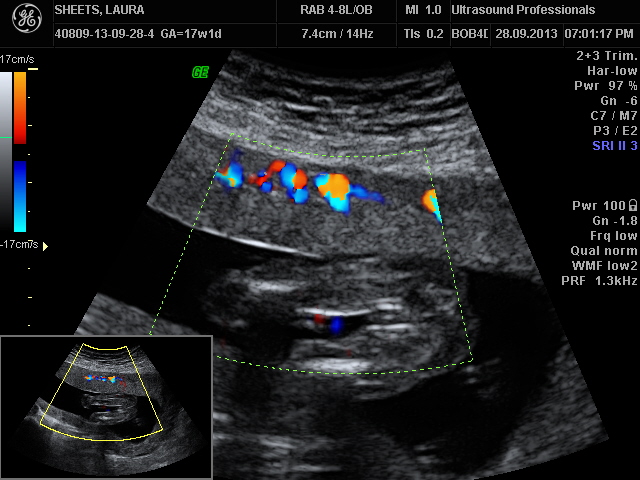

We just got these 2 u/s pics yesterday at our 17 week appointment. I realize they aren't the greatest, but my doc said based on what he saw he'd guess girl. He did say he wasn't 100% until we had our 20 week anatomy scan which will be much more hi-res than his equipment. Boo, 3 weeks feels like forever. SO in the meantime, anyone care to take a guess?

I honestly can't say. I agree with pp, there isn't three lines, but there isn't a penis either.